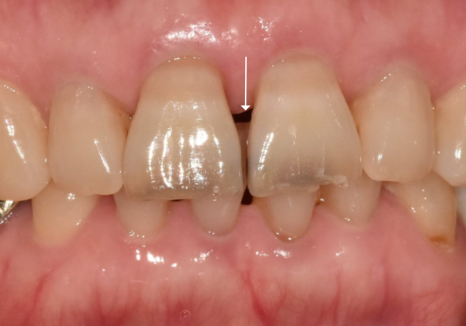

얼마 전 가운데 앞니(#11, 21)가 까맣게 변해서

걱정스러운 마음으로 내원하신 환자분이 계셨어요.

치아를 살펴보니

전체가 어둡게 변한 게 아니라,

마모된 끝부분 위주로

까맣게 변색된 모습이었습니다.

처음에는 치아 신경이 손상되어

'실활치 변색'은 아닐까 의심해 볼 수도 있는데요.

(실활치 변색: 외상 등으로 신경이 죽으면서

치아 색이 어둡게 변하는 현상)

하지만 이 환자분은 과거에

신경치료를 받으신 적이 전혀 없으셨고,

변색 역시 치아 전체가 아닌

마모된 끝부분에만 한정되어 있었어요.

여러 정황을 종합해 볼 때,

신경 문제라기보다는

마모로 인해 약해진 틈 사이로

충치가 진행된 것으로 판단되었습니다.